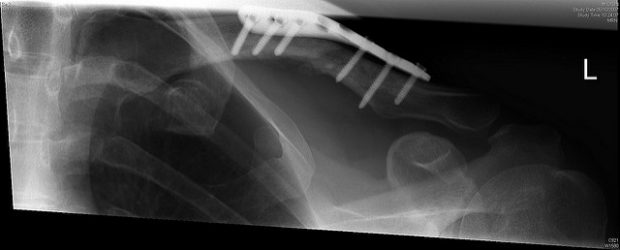

Implantate aus Titan unterstützen aktuell die Heilung von Knochenbrüchen. Foto:  How would I summarise 2007?, Oisin Mulvihill, Flickr, CC BY-SA 2.0

Bei komplizierten Knochenrekonstruktionen greifen Chirurgen auf Titanstifte, Schrauben oder gar Platten zurück, um den Knochen bei der Heilung zu stabilisieren. Diese müssen nach der Heilung nicht selten wieder entfernt werden, was mindestens eine weitere Operation erforderlich macht. Wissenschaftler des Fraunhofer-Instituts für Fertigungstechnik und angewandte Materialforschung (IFAM) in Bremen haben ein Material entwickelt, das bei Knochenrekonstruktionen zum Einsatz kommen kann und sich anschließend im Körper der Patienten abbauen. Somit können Kosten gesenkt und die Belastung für die Patienten verringert werden.

Das Material wurde bereits im Jahr 2014 erstmals auf einer Messe in Düsseldorf vorgestellt. Die Forscher demonstrierten ihre Entwicklung mittels eines Schulterankers, der abgetrennte Sehnen wieder mit dem Knochen verbindet. Der Anker selber ist kaum größer als ein Streichholzkopf, nach Abschluss des Heilungsprozesses werden sie für gewöhnlich jedoch wieder entfernt. Der neue Anker aus Metall-Keramik-Komposit (Eisen-Tricalciumphosphat) kann im Körper jedoch eigenständig abgebaut werden.